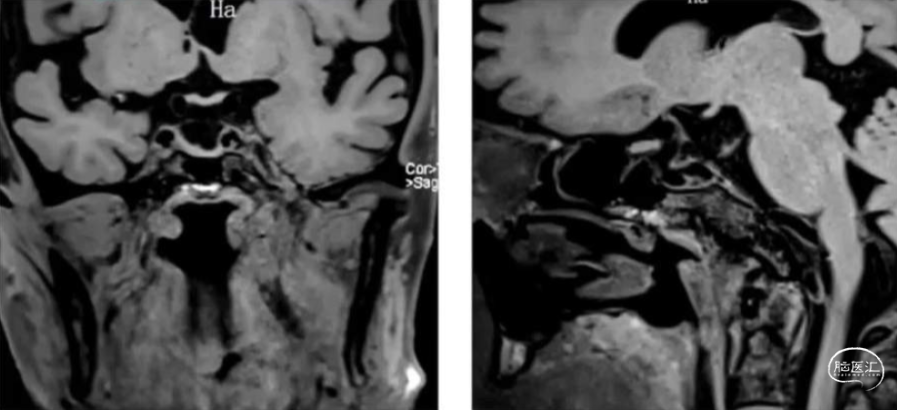

高分辨磁共振

1.动脉瘤形态不规则合并子囊,绝对宽径,需支架辅助

2.载瘤动脉近端狭窄

3.同侧A1发育不良